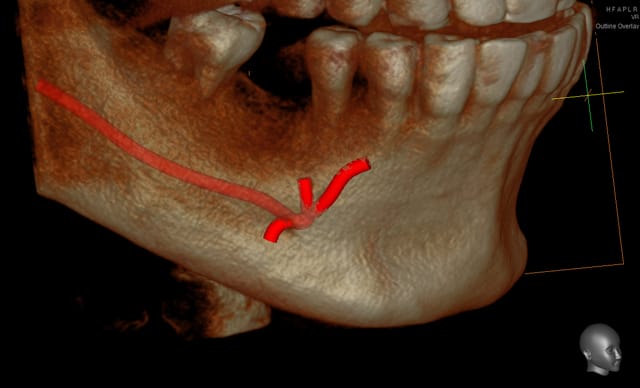

Est-ce qu'il y a une fonction de reconstruction 3d de l'anatomie canalaire du genre je clique et ça s'affiche ?

003 penrd2 - Eugenol

Cingulum

01/12/2011 à 16h09

oui, mais tu as intérêt a le faire en manuel. ça prend 20sec et tu es sure...